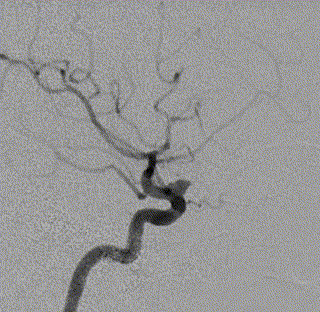

术后3月复查,瘤体未见显影,载瘤动脉通畅

同期4mm×20mm Streamline 进一步处理右侧动脉瘤